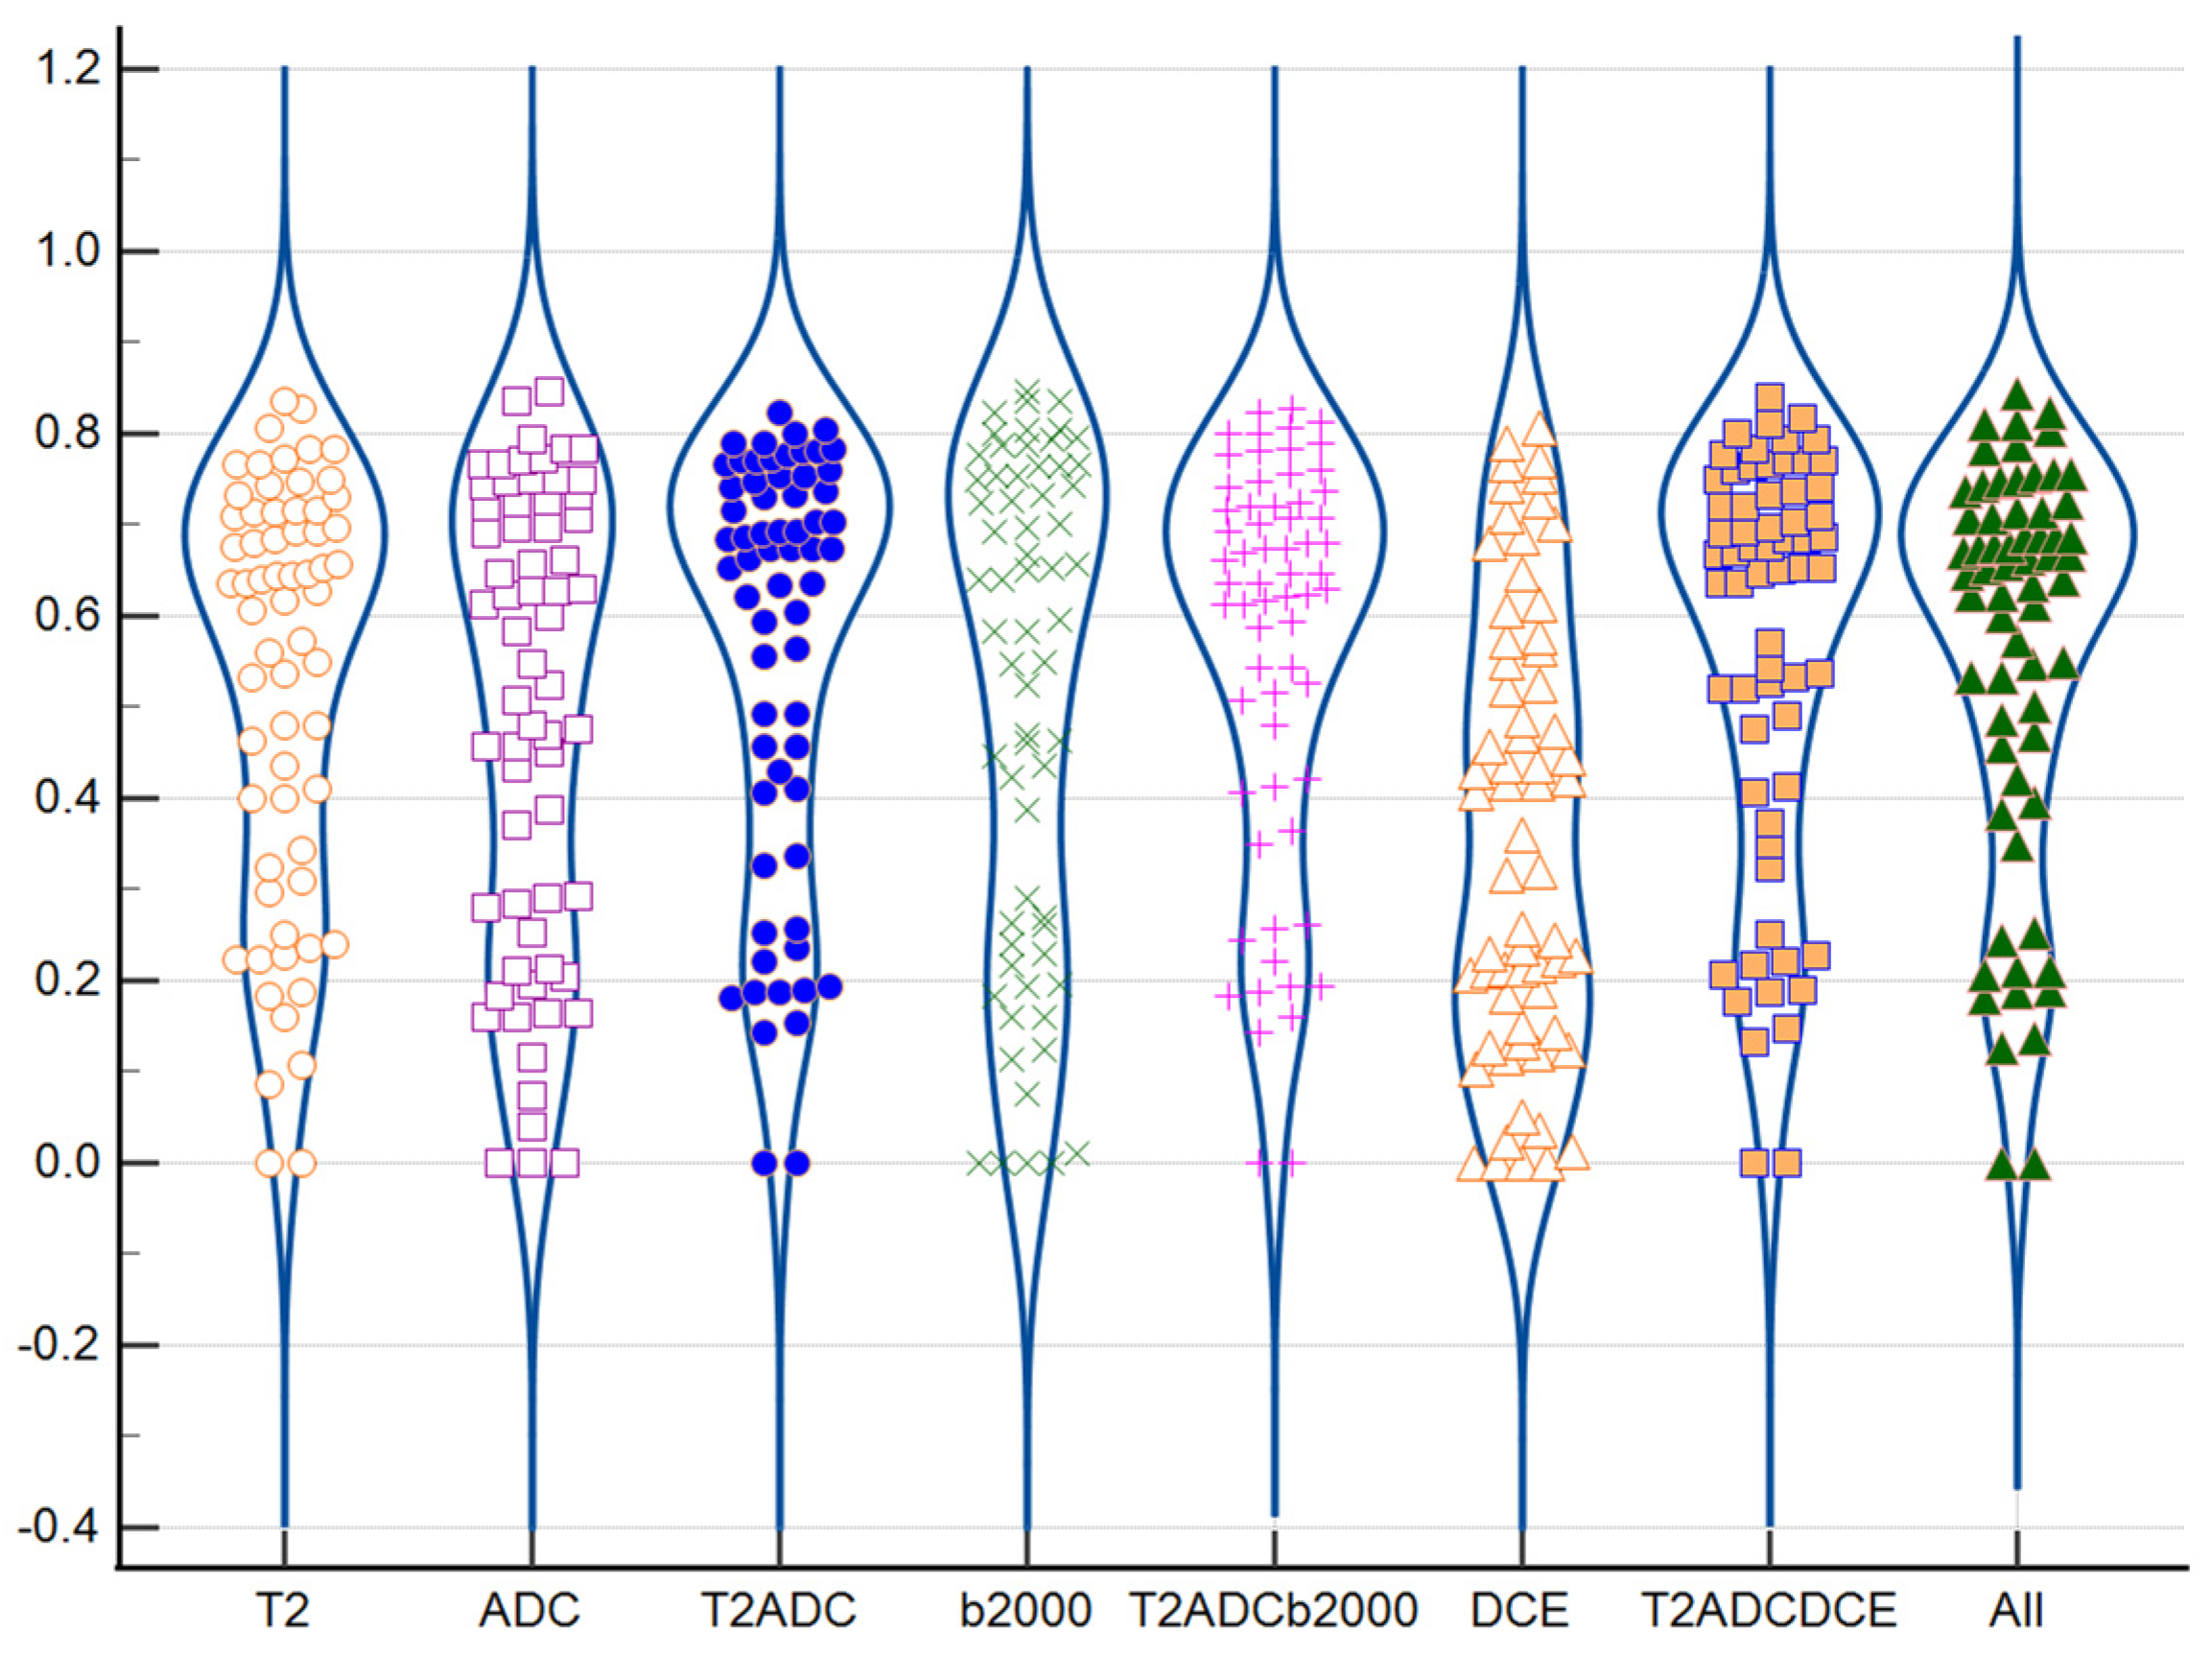

3.4. Impact of Tumoral Volume and PI-RADS Classification